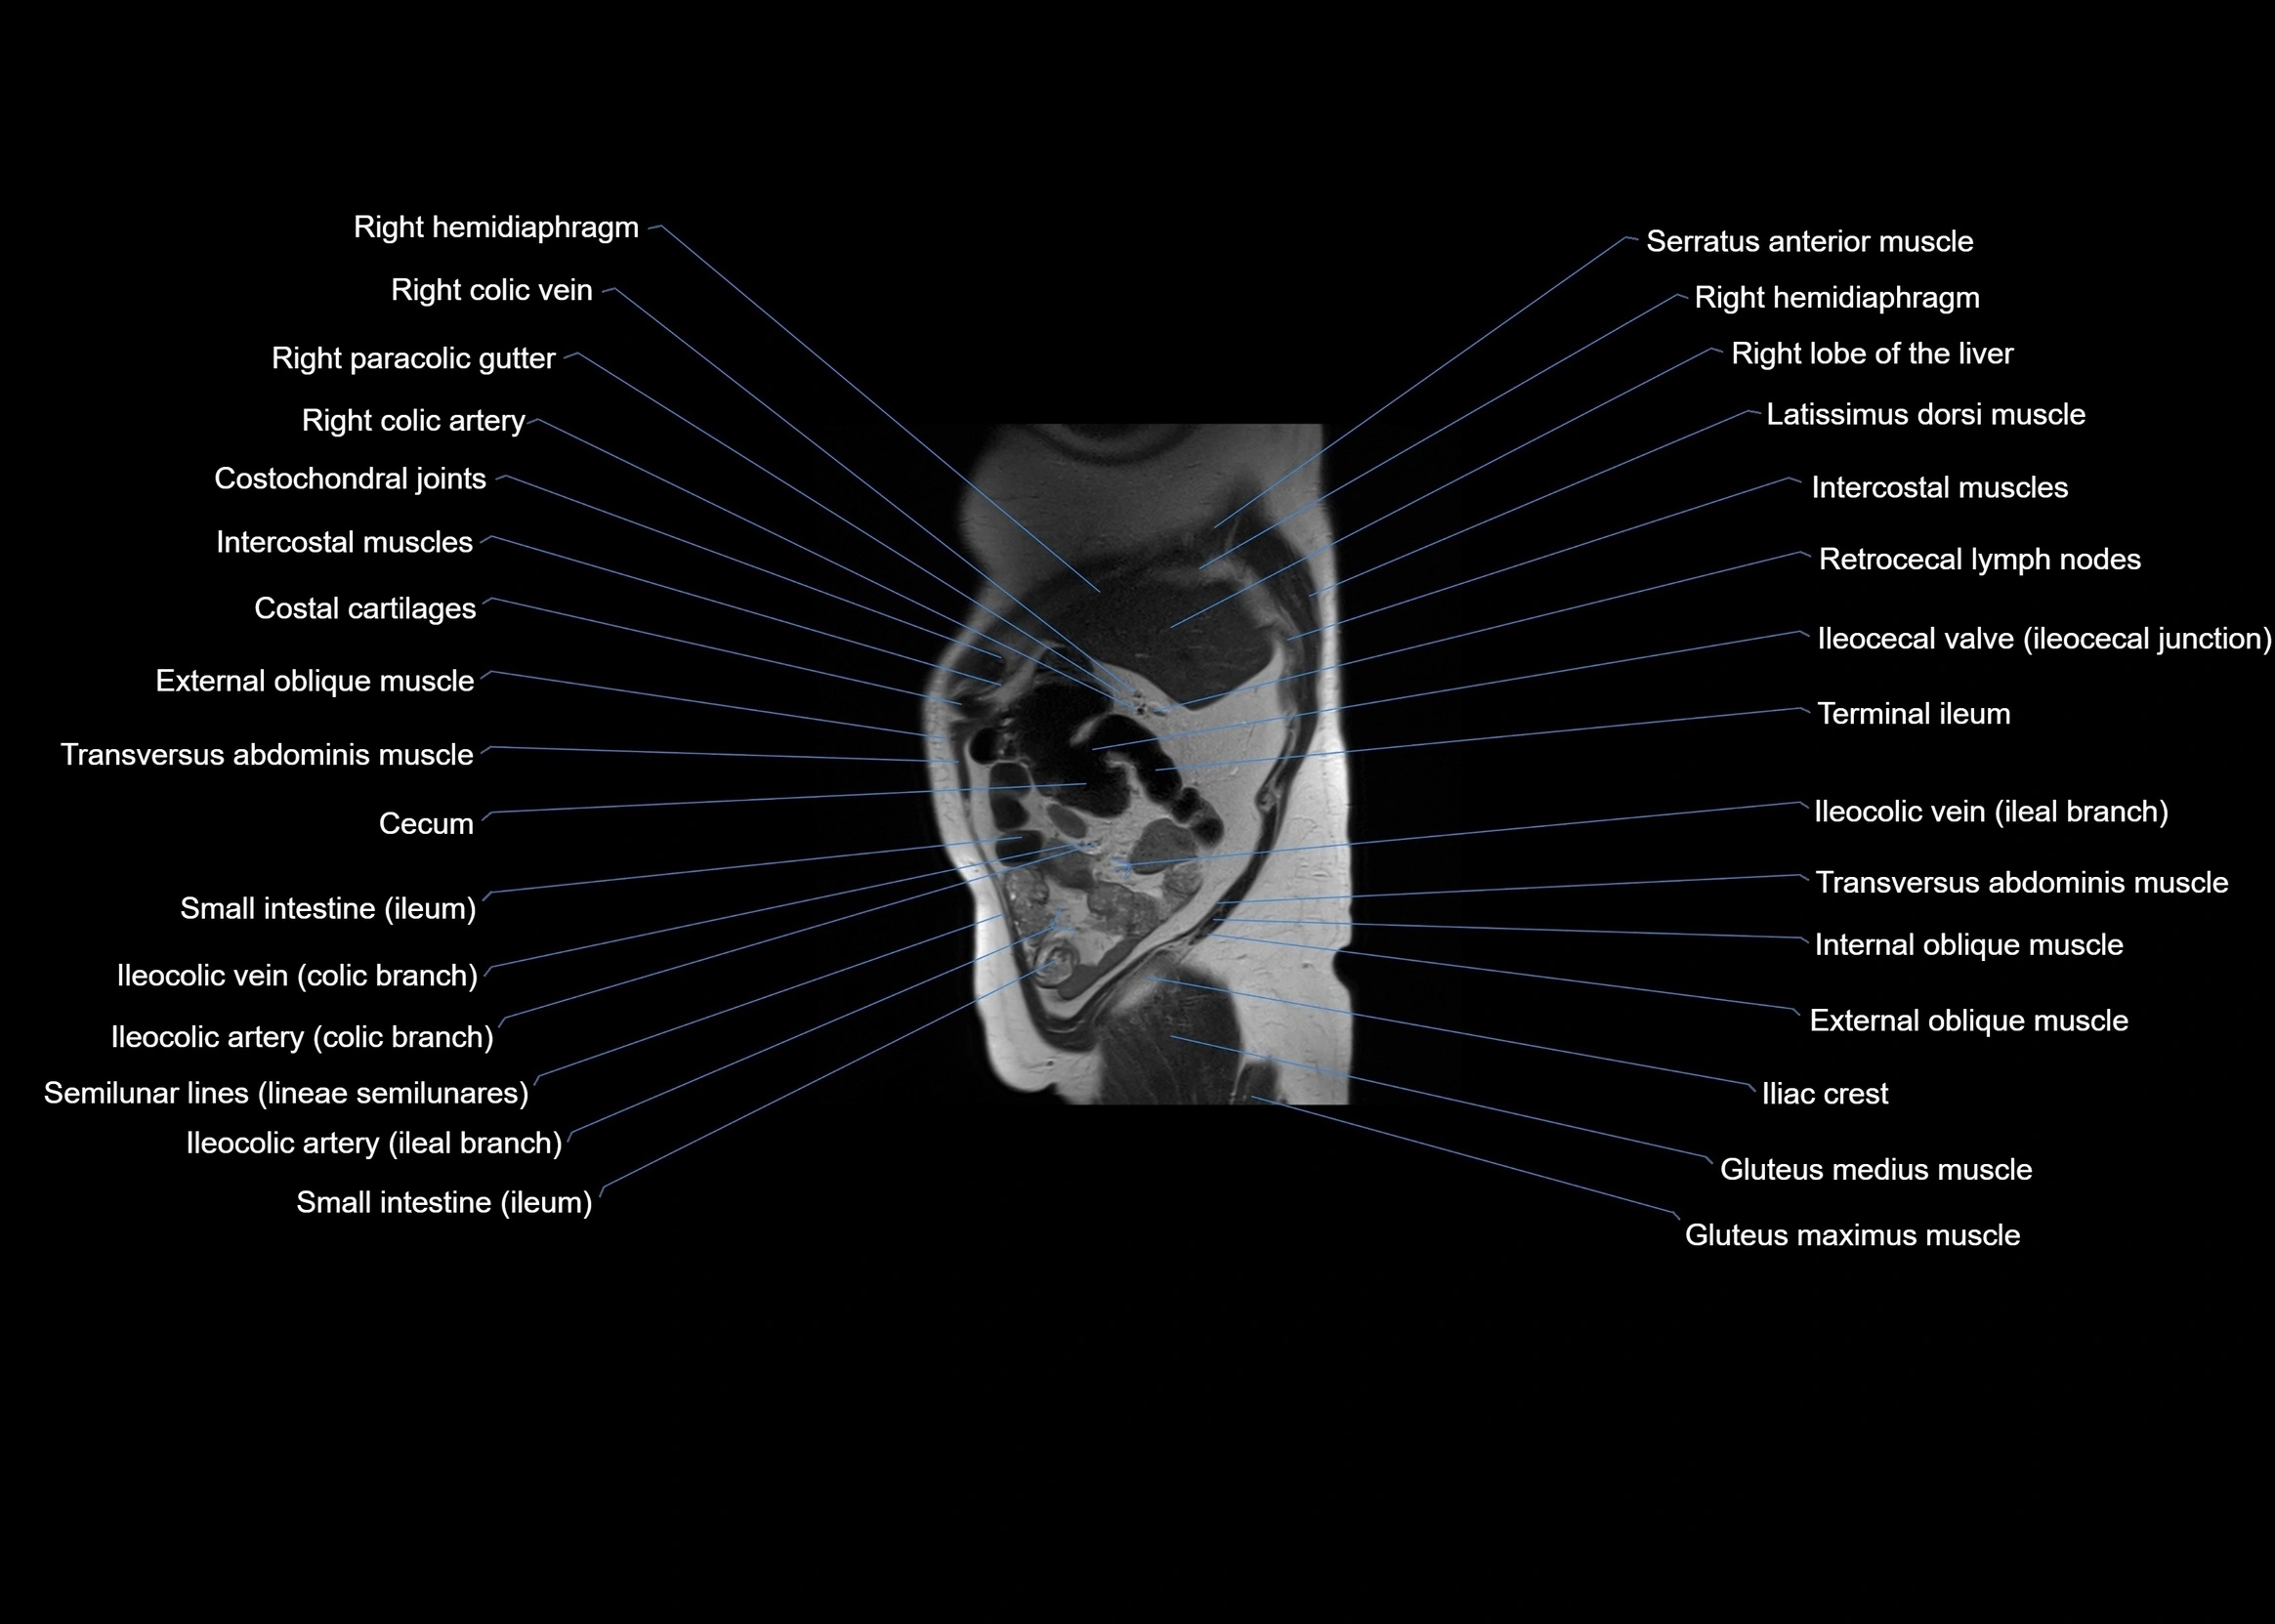

MRI images